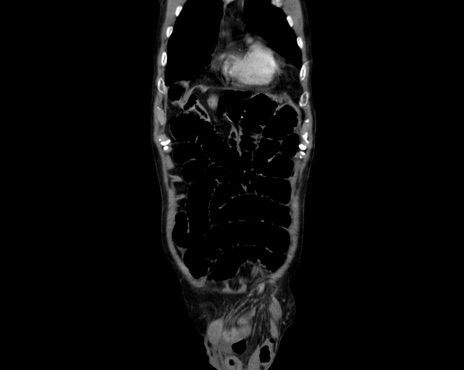

症例26(冠状断像)

【症例】80歳代男性

【主訴】嘔吐

【現病歴】昨晩2回嘔吐あり、今朝になっても嘔吐あり。来院。

【既往歴】胃潰瘍

【身体所見】意識清明、BT 37.6℃、BP 166/95mmHg、HR 100bpm、SpO2 97%、腹部:平坦・軟、腸蠕動音聴取良好、圧痛なし。

【データ】WBC 21900、CRP 1.4